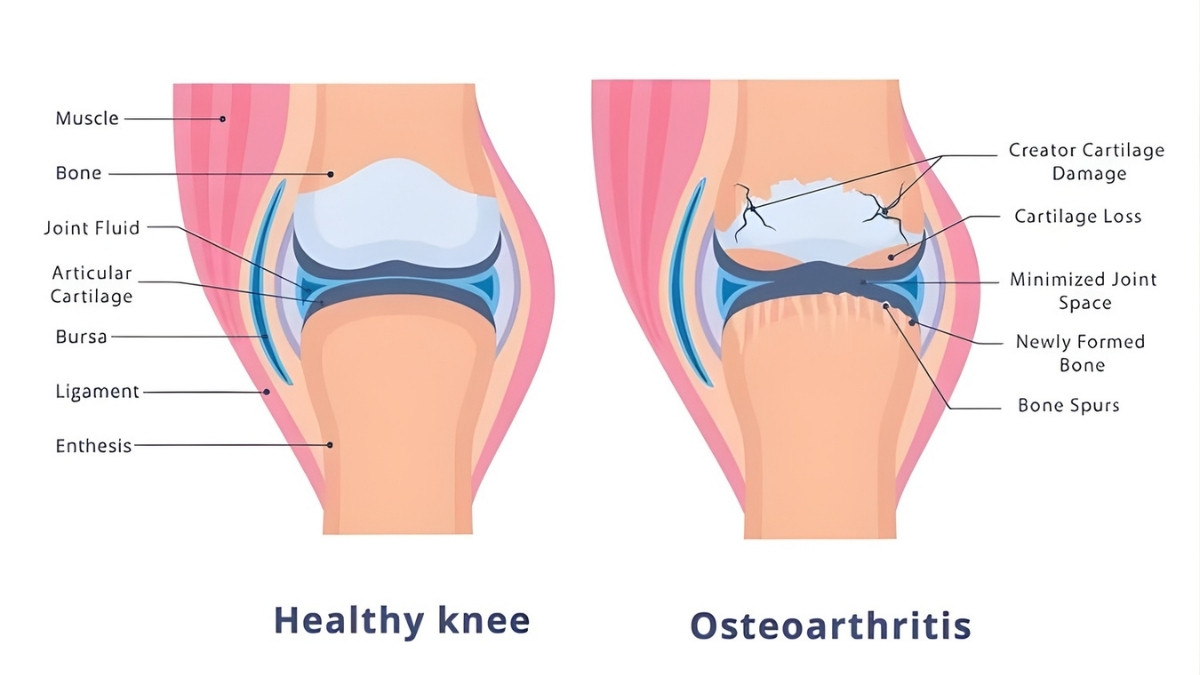

How High Blood Sugar Destroys Cartilage: The AGE-RAGE Connection

Your cartilage cells have glucose transporters called GLUT1. They let sugar in for energy. Normal amounts work fine. But when blood sugar stays high, these transporters become weapons.

Here’s what happens. Excess glucose enters your cartilage cells. It sticks to proteins permanently. These sticky proteins are called Advanced Glycation End Products—AGEs for short. Think of rust forming on metal. AGEs do the same thing to your cartilage. They make it stiff and brittle.

AGEs bind to receptors called RAGE. This triggers an inflammatory explosion. Your cells release TNF-α and IL-1β. These signals tell your body to break down cartilage. Enzymes called MMPs (matrix metalloproteinases) start destroying the cushioning in your joints. At the same time, Reactive Oxygen Species damage your cell DNA and proteins.

The research from Experimental & Molecular Medicine (June 2022) showed something scary. OA cartilage cells can’t turn down their glucose transporters. Even in high-sugar environments. This means constant damage. Diabetes patients have 20% higher rates of joint replacement surgery. Fasting glucose levels directly match knee damage on MRI scans.